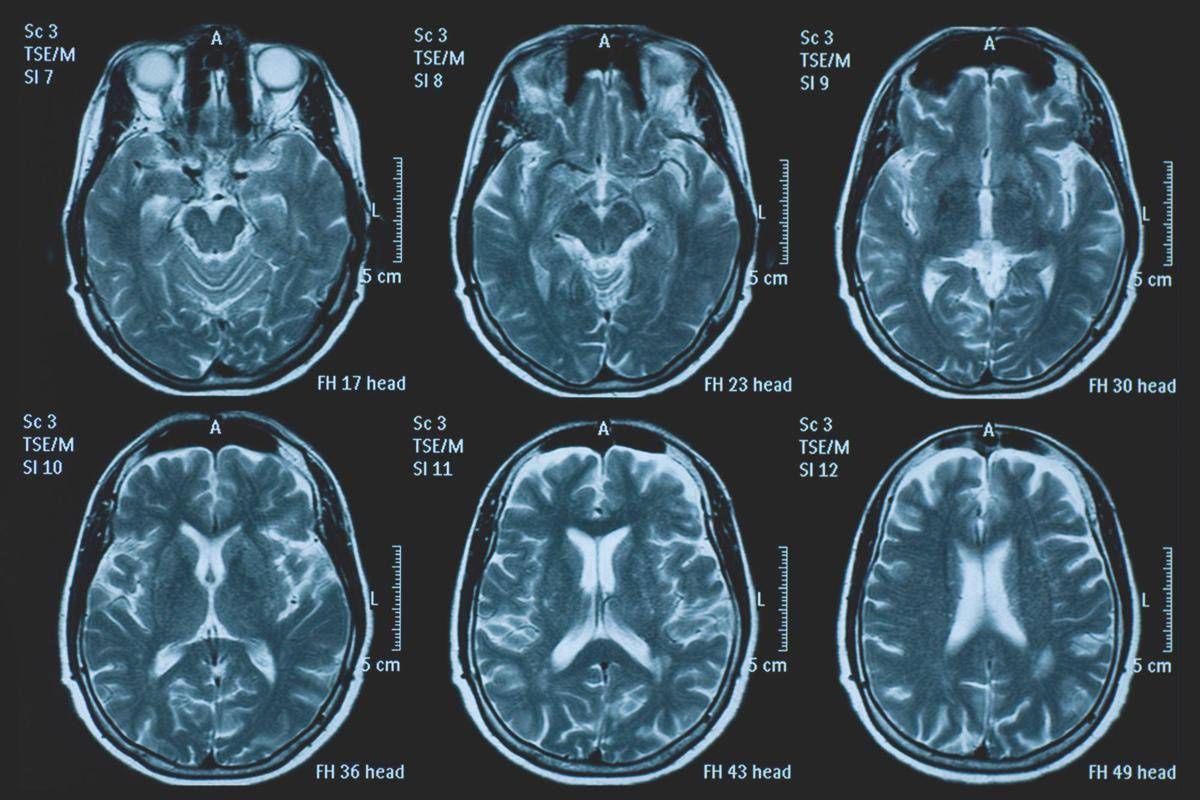

(Adnkronos) – La Commissione europea (Ce) ha autorizzato la commercializzazione condizionata di tovorafenib come monoterapia per il trattamento dei pazienti di etĂ pari o superiore a 6 mesi con glioma pediatrico di basso grado che presentano una fusione o un riarrangiamento del gene Braf o una mutazione Braf-V600, in progressione di malattia dopo una o piĂą terapie sistemiche precedenti. Lo annuncia Ipsen, in una nota, precisando che si tratta della “prima terapia mirata” per questa patologia e che la decisione della Ce si riferisce ai 27 Stati membri della Ue, oltre a Islanda, Liechtenstein e Norvegia. Ogni anno in Ue vengono diagnosticati piĂą di 800 nuovi casi di glioma pediatrico di basso grado (pLgg) con alterazione di Braf. Questo tumore cerebrale, nonostante sia classificato di basso grado (a lenta progressione), comporta un carico significativo e permanente che accompagna la persona per tutta la vita, causando spesso importanti compromissioni fisiche e neurologiche, tra cui perdita della vista, difficoltĂ di linguaggio e disfunzioni motorie, che possono incidere in modo significativo sull’istruzione, l’autonomia e la qualitĂ di vita a lungo termine del bambino. Finora, molti bambini con pLgg hanno dovuto sottoporsi a interventi chirurgici invasivi, a piĂą cicli di chemioterapia e a radioterapia, con conseguenti complicazioni della salute.Â

L’approvazione della Ce si basa sui dati dello studio di fase 2 Firefly-1 che ha valutato tovorafenib in 137 bambini e giovani adulti con pLgg recidivato o refrattario con alterazioni di Braf che avevano ricevuto almeno una precedente terapia sistemica. Nel dettaglio, lo studio ha dimostrato una risposta tumorale clinicamente significativa con un tasso di risposta globale del 71% secondo i criteri Rano-Hgg (ResponseAssessment in Neuro-Oncology criteria for High-Grade Gliomas) e del 53% secondo i criteri Raono-Lgg (Response Assessment in Paediatric Neuro-Oncology for Low-Grade Glioma), con un tasso di beneficio clinico del 77% secondo i criteri Rano-Hgg e del 58% secondo i criteri Rapno-Lgg. Le risposte – riferisce la nota – sono state rapide e durature: sulla base dei criteri Rapno-Lgg, tra coloro che hanno risposto, il tempo mediano alla risposta è stato di 5,4 mesi con una durata mediana della risposta di 18 mesi.Â